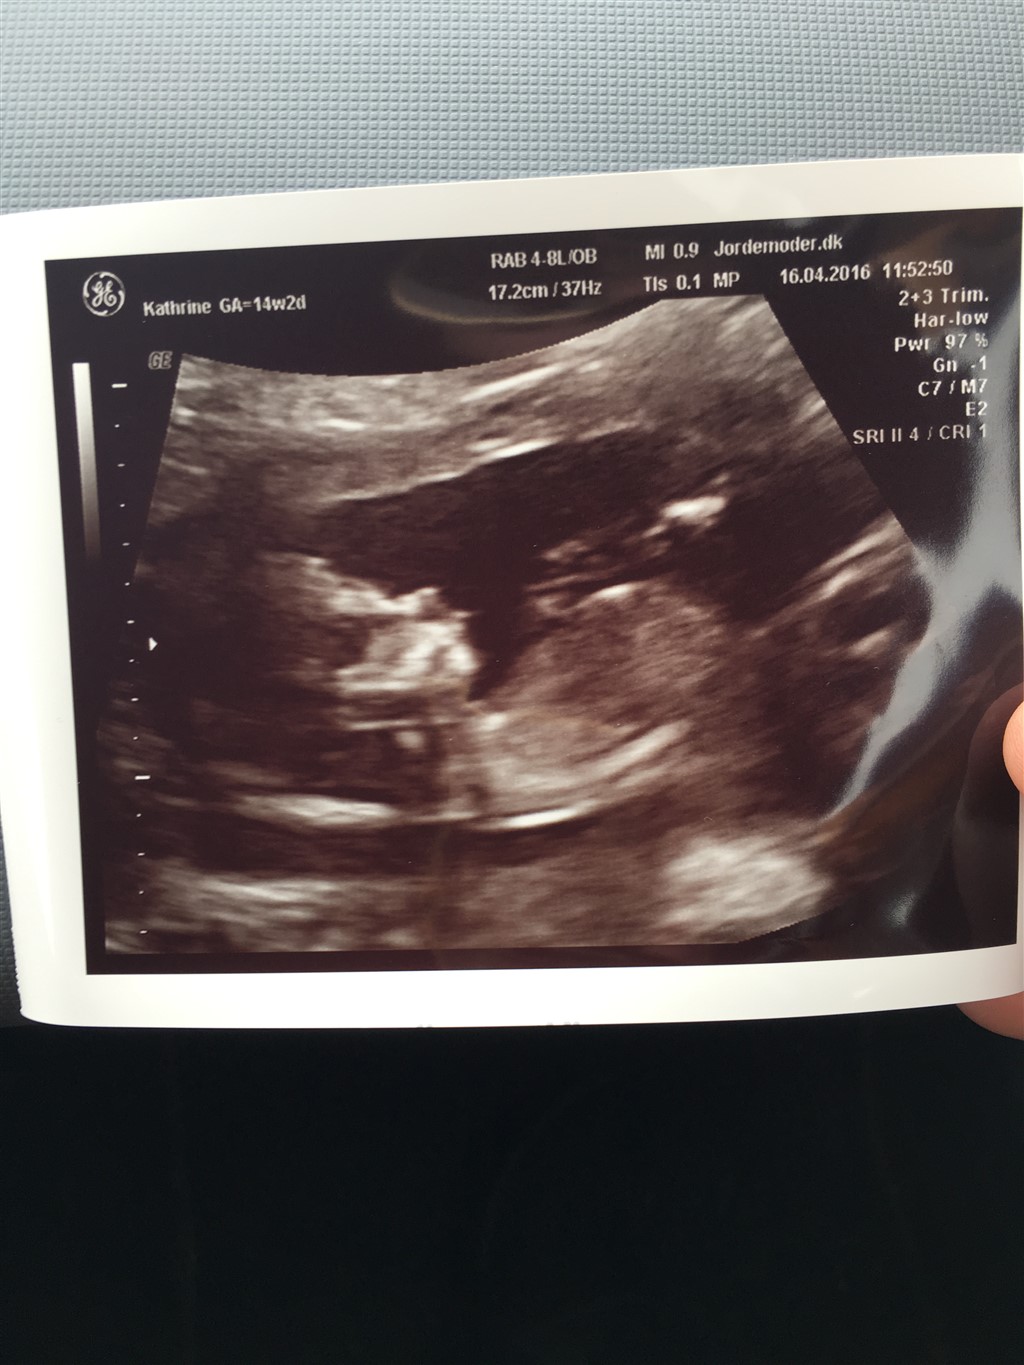

vi var til kønsscanning i dag og det er sørme en lille pige, der gemmer sig i hulen

Vedhæftede fotos (klik for at se i fuld størrelse)